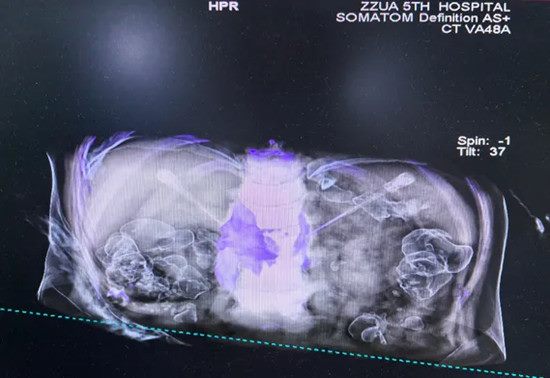

▲ 术中穿刺针到达

▲ 注射靶点影像